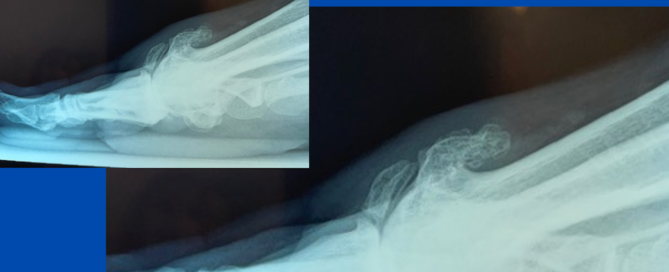

Fractured bone spur

Blog's main page This patient presented in early March with a history of a sudden severely inflamed and painful right 1st MTPJ after a run completed the previous month. The [...]